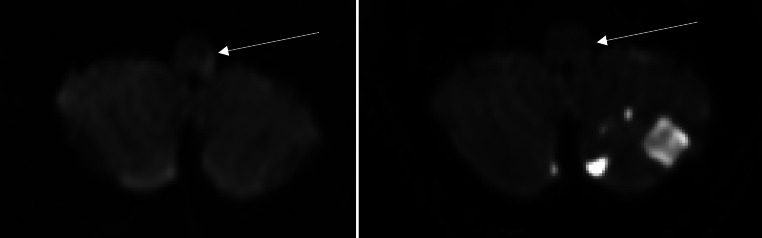

目的:弥散加权成像(DWI)表征急性缺血性脑卒中的梗死核心。DWI可逆性是一种影响脑白质小区域的前循环的现象。本研究旨在明确基底动脉闭塞(BAO)再通成功后后循环DWI可逆性及其对患者预后的影响。方法:回顾性分析2015年1月至2022年12月对脑卒中患者进行分析的两个三级脑卒中中心。纳入标准为急性脑卒中治疗前后MRI及BAO再通成功。脑区被定义为脑干、小脑和幕上脑由后循环供应的脑区。在单因素分析中对这些区域进行比较。其次,比较DWI可逆性患者和无DWI可逆性患者的预后,单因素分析以预后良好为主要终点(mRS 90d 0 ~ 2)。结果:总共有5/28的纳入患者(21.74%)显示DWI可逆性,DWI可逆性仅发生在脑干。与小脑或幕上梗死相比,脑干梗死的总体范围与患者预后的相关性更好(Spearman ρ = 0.757;p 结论:急性脑卒中合并BAO患者脑干DWI限制可逆性明显。在这项研究中,与小脑或幕上梗死相比,患者预后与脑干梗死的范围相关性更强。

Results: In total, 5/28 of included patients (21.74%) showed DWI reversibility, which was exclusively found in the brainstem. The overall extent of brainstem infarction correlated better with patient outcome compared to cerebellar or supratentorial infarction (Spearman's ρ = 0.757; p < 0.001). Good outcome was more frequent in patients with DWI reversibility compared to those without (mRS 0-2, DWI+ n = 4, 80% vs. DWI- n = 6, 26%, p = 0.023).

Conclusion: DWI restriction reversibility was observed in the brainstem of acute stroke patients with BAO. In this study, patient outcome correlates stronger with the extent of brainstem infarction compared to cerebellar or supratentorial infarction.